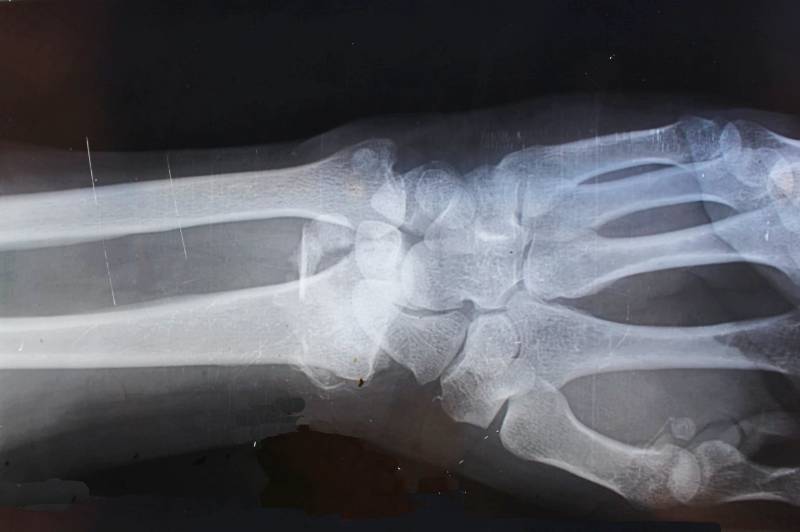

나이가 들수록 뼈 건강은 삶의 질을 좌우하는 중요한 요소가 됩니다. 특히 골다공증이나 골절은 노년기에 흔히 나타나는 문제로, 일상생활에 큰 불편을 주고 회복도 더딜 수 있습니다. 많은 사람들이 뼈가 약해지는 이유로 칼슘이나 비타민 D의 부족을 원인으로 떠올리지만, 실제로는 다양한 생활습관, 질병, 호르몬 변화 등 여러 요인이 복합적으로 작용합니다. 특히 뼈가 약해지기 시작하면 눈에 띄는 증상이 없기 때문에 예방이 무엇보다 중요합니다.

뼈가 약해지는 원인은 단순히 나이 때문만이 아니라, 영양 상태, 호르몬 변화, 생활습관, 질환, 흡연·음주 등 다양한 요인이 복합적으로 작용합니다. 하지만 다행히도 이런 요인들은 상당 부분 생활습관 개선과 예방적 관리로 조절할 수 있습니다.